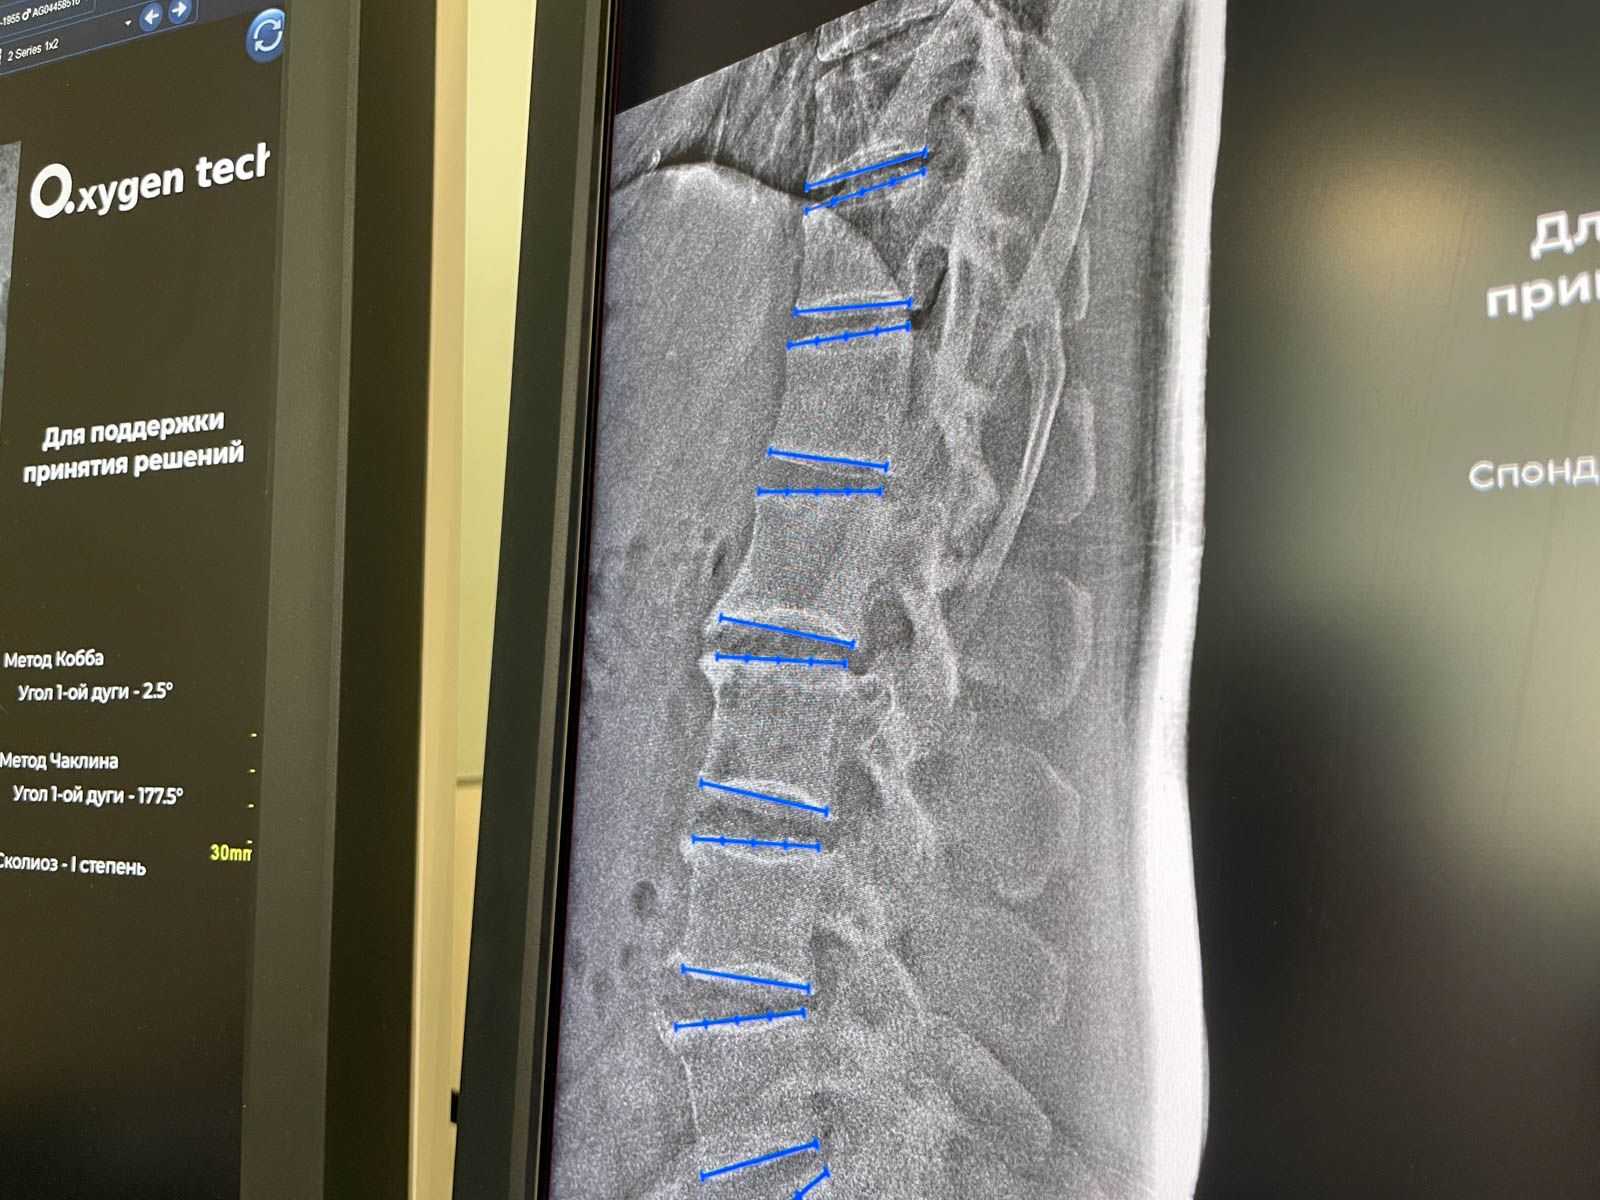

Смещение тел позвонков — это патологическое состояние, которое может вызывать сильные боли в спине и существенно снижать качество жизни. Для его точной диагностики врачи теперь могут прибегнуть к помощи ИИ, который автоматически анализирует рентгенограммы, выявляет признаки смещения и проводит необходимые измерения. Такая автоматизация не только уменьшает время подготовки заключения, но и обеспечивает высокую точность диагностики.

С момента начала использования ИИ-сервисов в медицинской практике было обработано более 12 миллионов исследований. Нейросети помогают выявлять признаки множества патологий, включая рак легкого, пневмонию, остеопороз, аневризму аорты, ишемическую болезнь сердца, инсульт и другие заболевания. Это стало возможным благодаря работе Центра диагностики и телемедицины Департамента здравоохранения города Москвы, где ведется постоянный мониторинг точности и эффективности алгоритмов.